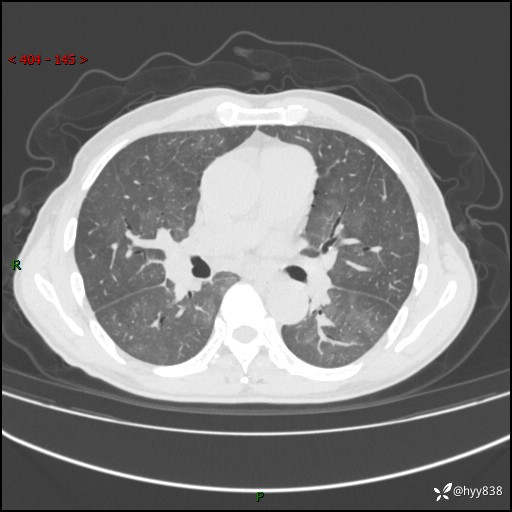

肺结节入院,CT却发现肺部弥漫性病变,what happened---(有结果)

辅助检查:CT

胸部CT平扫

不是讨论肺部结节